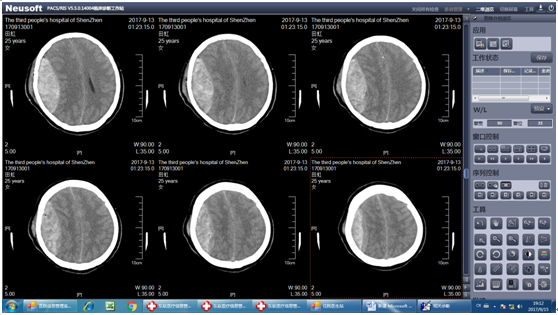

此时田某神志昏迷,口吐白沫,病情恶化迅速,情况危急,双侧瞳孔直径散大,脑疝形成,死亡率极高。我院神经外科唐忠主任与陈思、廖广生医师迅速为田某急诊行开颅右侧硬膜外血肿清除术+去骨瓣减压术。术程顺利,患者右侧额颞顶巨大硬膜外血肿完全清除,术中见静脉窦破裂,予以彻底止血,手术顺利。术后考虑病情危重由手术室送入综合ICU监护治疗。予呼吸机辅助通气,保持右侧头部硬膜外血肿引流管通畅、止血、预防感染、预防应激性溃疡、维持水电解质平衡、防止并发症、防止深静脉血栓形成等治疗。经过治疗后田某病情好转,术后第二天患者神志清楚,生命体征平稳,转回我科科继续治疗,现患者病情正在逐步恢复好转。

术后头颅CT